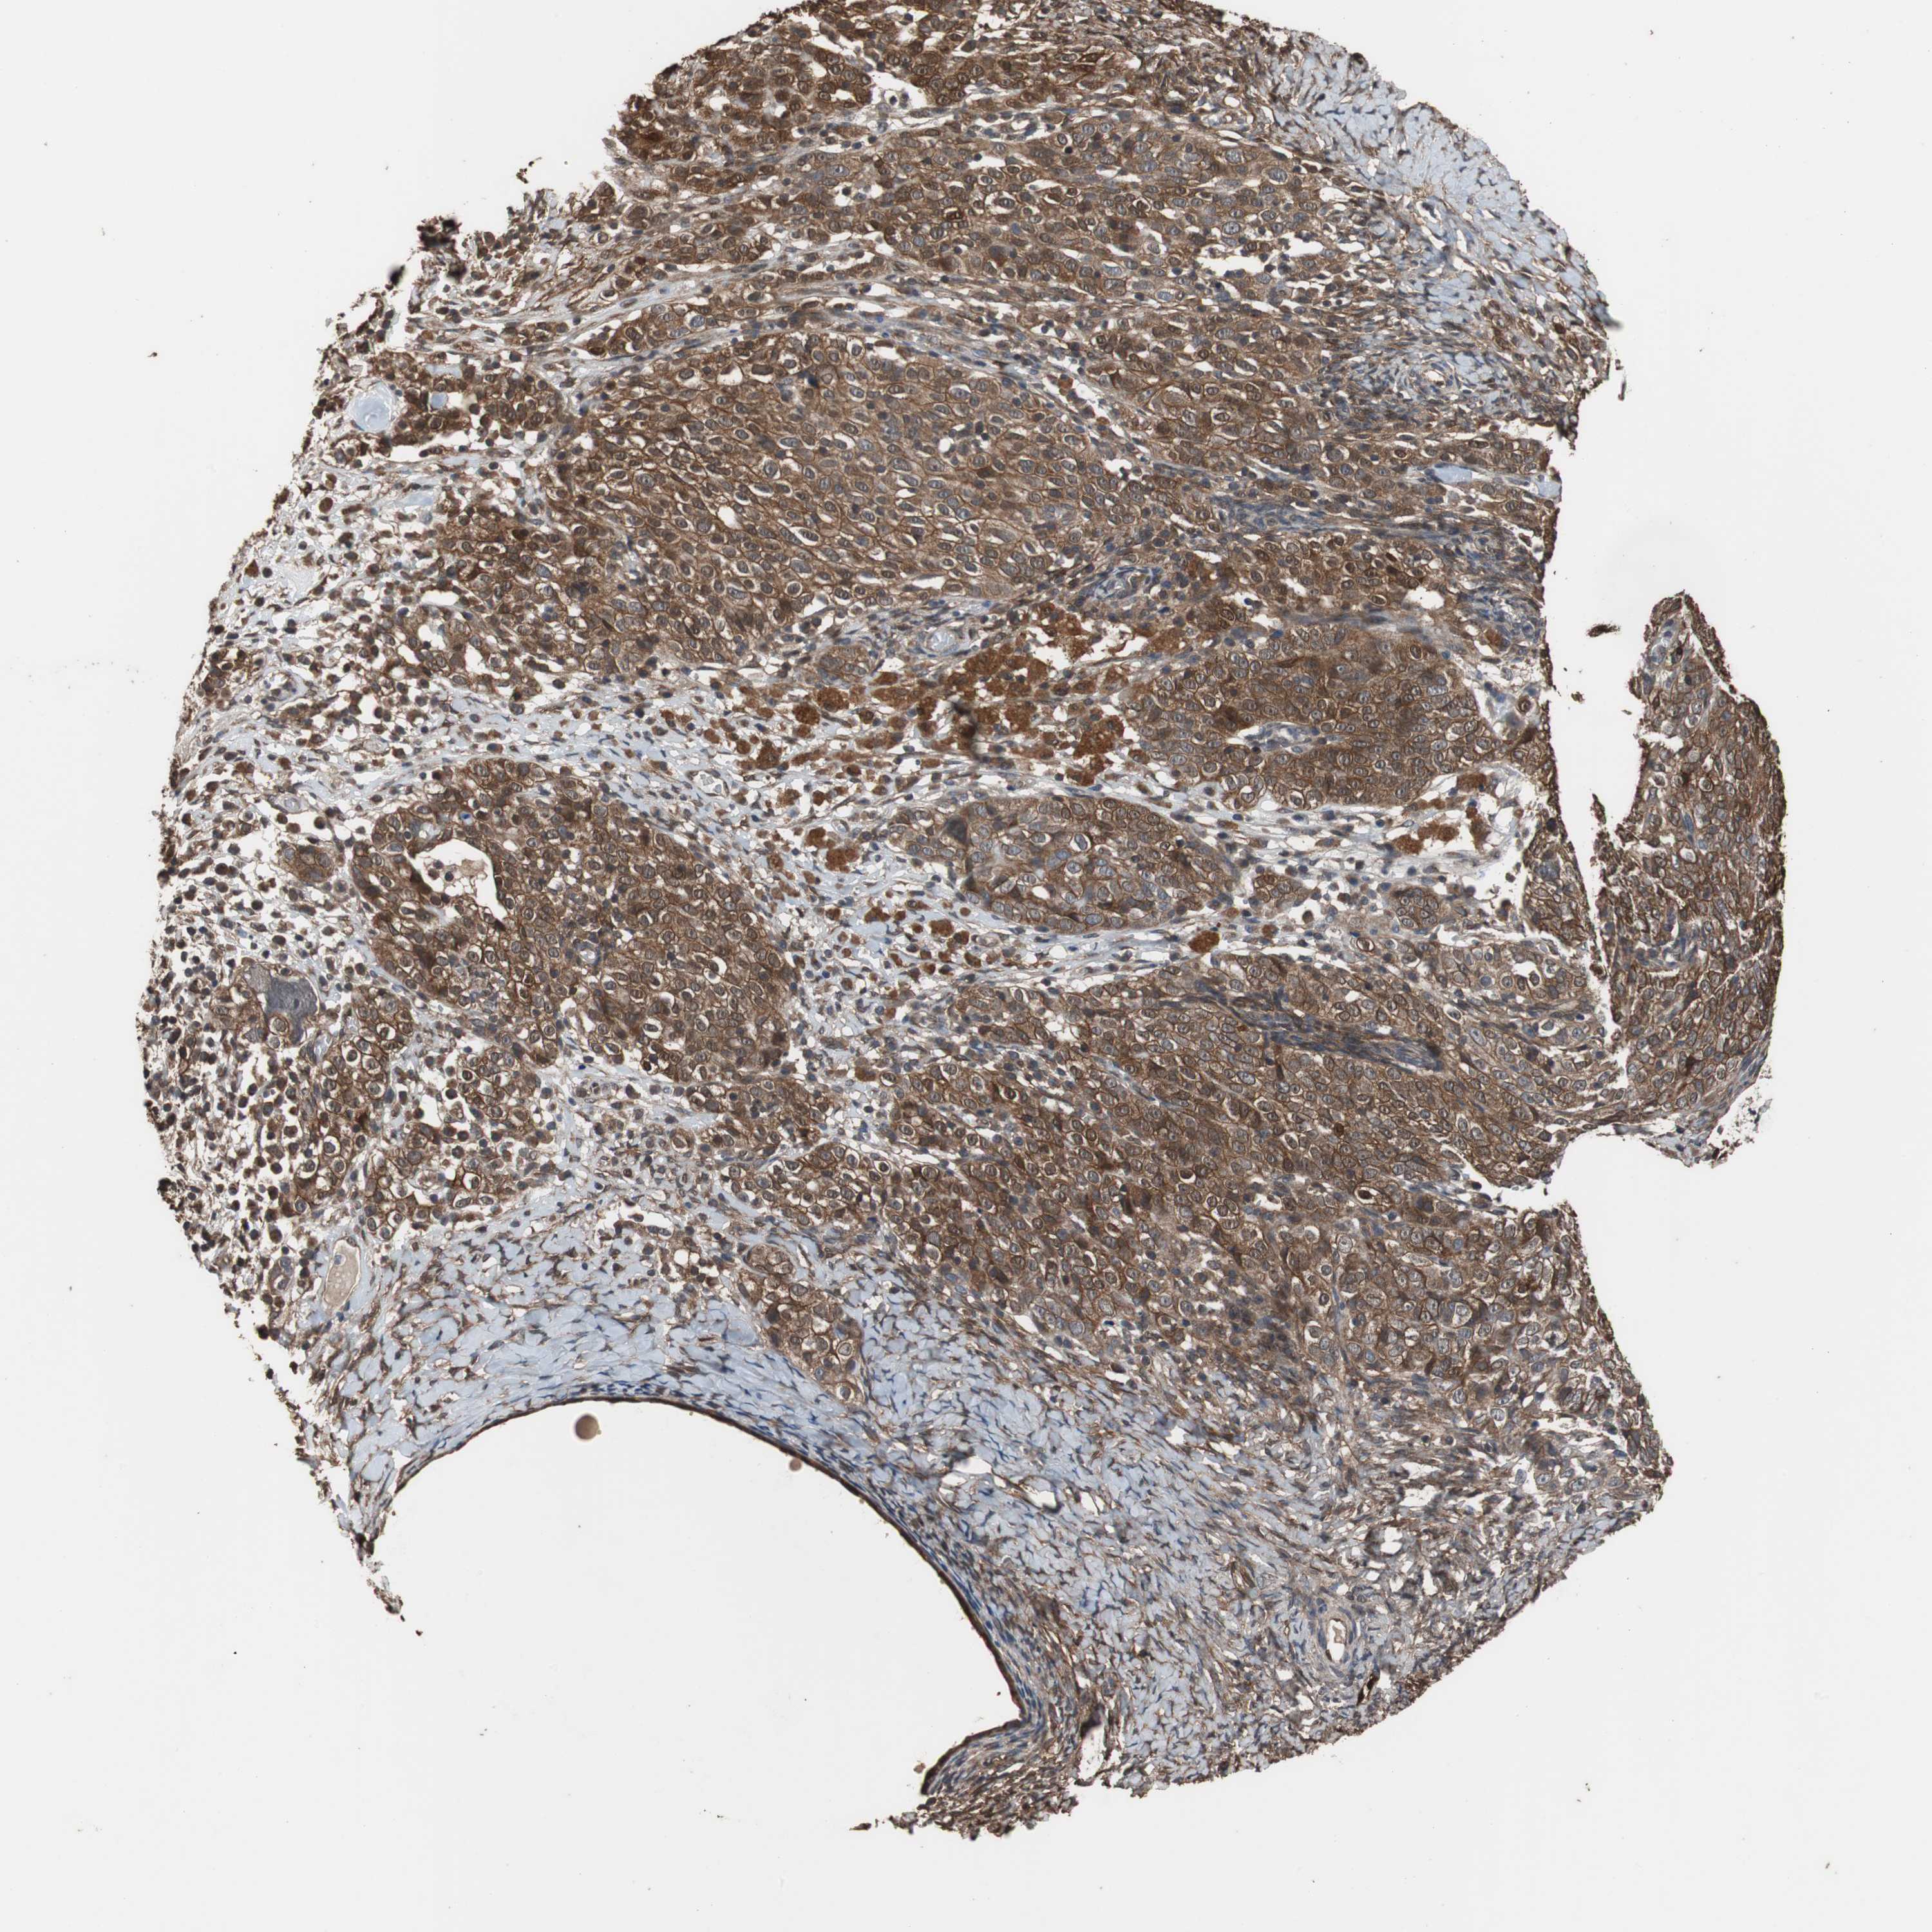

OVARIAN CANCER - Protein expressioni

A mouse-over function shows sample information and annotation data. Click on an image to view it in a full screen mode. Samples can be filtered based on level of antibody staining by selecting one or several of the following categories: high, medium, low and not detected. The assay and annotation is described here.

Note that samples used for immunohistochemistry by the Human Protein Atlas do not correspond to samples in the TCGA dataset.

Antibody stainingi

Antibody staining in the annotated cell types in the current human tissue is reported as not detected, low, medium, or high, based on conventional immunohistochemistry profiling in selected tissues. This score is based on the combination of the staining intensity and fraction of stained cells.

Each image is clickable and will lead to virtual microscopy that enables deeper exploration of all samples and also displays staining intensity scores, fraction scores and subcellular localization as well as patient and tissue information for each sample.

Antibody HPA006881

Cystadenocarcinoma, serous, NOS

Cystadenocarcinoma, mucinous, NOS

Carcinoma, endometroid